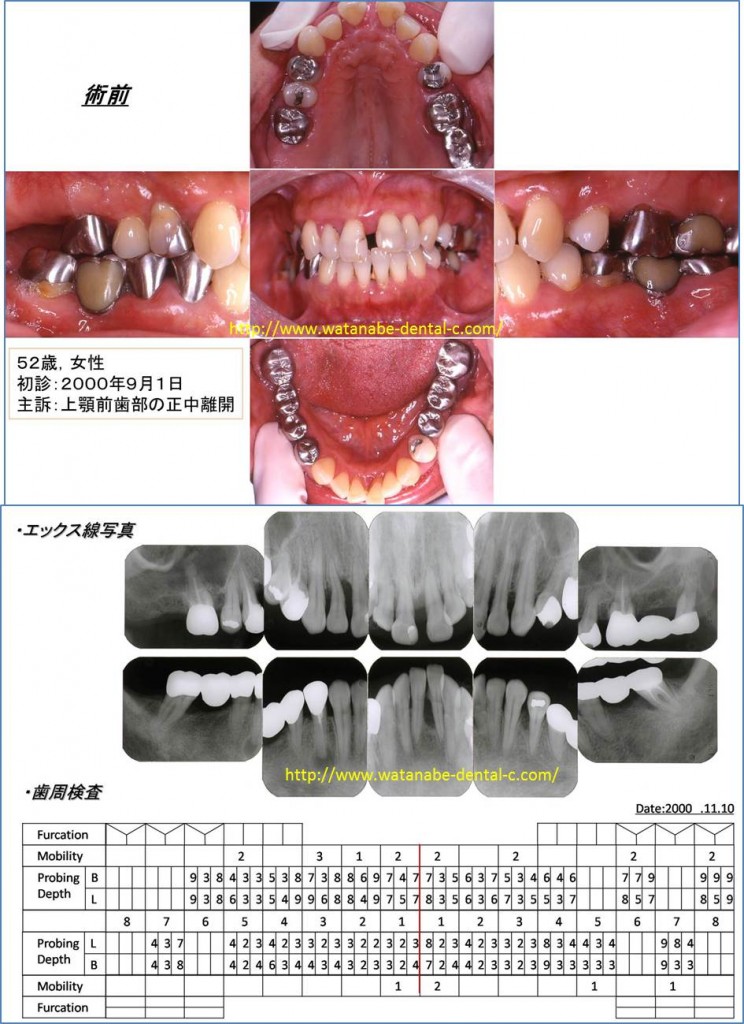

2.歯周病症例(主訴:前歯の開きが気になる。)

52歳女性、上の前歯が開いていることが気になり来院されました。前歯の間が開き、歯肉が腫れています。エックス線撮影、歯周ポケットの検査を行っています。全体的に5mm以上の歯周ポケットが認められます。このような場合、開いてしまった歯を削って冠を被せてしまえば、解決するのでしょうか?それでは解決しません。見た目の問題を解決しても、歯肉の中の根が汚染されていれば、冠を被せて一時的に見た目が回復しても、また開いてきてしまいます。そこで「治療計画」を立案します。ホームページでも示したように歯周病治療に限らず、歯科治療は「治療計画」がとても重要になります。その治療計画は「歯周病治療」をベースとしたものでなければならないと私は考えています。

では、この症例の場合の「治療計画」はどうすればいいのでしょうか?

まずは、歯周基本治療である炎症性因子のコントロールを行います。患者さんに1.歯間ブラシ、2.歯ブラシ、3.ワンタフトブラシにてブラッシング指導、スケーリング(歯石をとること)、スケーリング・ルートプレーニング(歯肉の中の根に付いている歯石をとり、汚染した根をきれいにすること)、不良な被せものを外して仮の歯の製作、左上の一番奥の歯は保存できないため抜歯。その後、再評価をします。歯周病治療では、この「再評価」がとても重要になります。「再評価」は、再度、歯周ポケット検査、歯の動揺、噛み合わせの確認を行います。この時点で歯周ポケットが改善されれば、歯周病治療は経過をみながら、被せものの治療へと移行します。しかしながら、特に奥歯に関しては歯周基本治療だけでは歯周ポケットは改善しにくいのです。「歯周基本治療」は「原因除去療法」といいます。歯の表面のプラークの除去、歯肉の中の歯肉縁下歯石の除去、無理な噛み合わせの調整により歯周病の原因および悪化させている原因を除去します。これで治れば一番良いのですが、まだ歯周ポケットが残っている場合は、「歯周外科処置」へ移行するのが望ましいです。この症例の場合、奥歯に関しましては歯肉剥離掻爬術を施行しました。

術後の写真と、歯周ポケット検査です。気になって来院された上の前歯の開きは改善しています。これは矯正治療を行ったわけではありません。上の前歯に関しては歯周外科処置も行っていません。患者さん自身の歯間ブラシ、歯ブラシ、ワンタフトブラシによるプラークの除去と来院されて行った「スケーリング・ルートプレーニング」により炎症を起こしていた因子が除去され、歯が自然と元の位置に戻りました。炎症は、歯をも動かしてしまうのです。炎症が改善すれば、歯の動揺が改善し、歯が自然と元の位置に戻ってくることがよくあります。歯周基本治療をきちんと行い、炎症を起こしている原因を除去することが最も重要になります。歯周ポケットも全体的に3mm以下に改善しました。